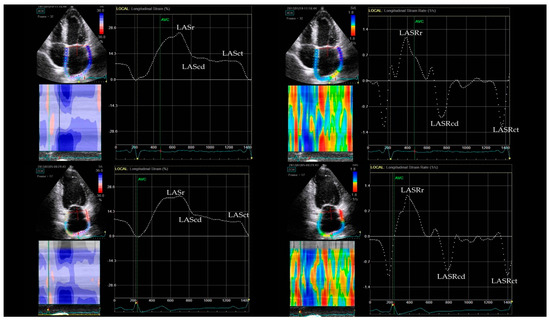

2.2. Echocardiography

| LASr (%) | 27.8 ± 6.9 | 27.8 ± 6.2 | 0.0 (−1.3; 1.1) | 0.91 |

| LAScd (%) | 15.0 ± 4.8 | 14.2 ± 4.2 | −0.8 (−1.7; 0.1) | 0.06 |

| LASct (%) | 12.8 ± 4.5 | 13.6 ± 3.7 | 0.8 (−0.3; 1.8) | 0.14 |

| LASRr (s−1) | 1.1 ± 0.3 | 1.3 ± 0.3 | 0.1 (0.1; 0.2) | <0.001 |

| LASRcd (s−1) | 1.1 ± 0.3 | 1.2 ± 0.3 | 0.1 (0.1; 0.2) | <0.001 |

| LASRct (s−1) | 1.4 ± 0.5 | 1.5 ± 0.7 | 0.0 (−0.0; 0.2) | 0.20 |